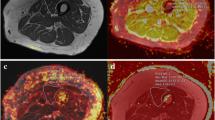

Regions of interest (ROIs) were contoured using Osirix imaging software (version 4.0; open-source DICOM viewer, https://osirix-viewer.com). Regions depicting the individual hamstring and quadriceps muscles were drawn on the middle slice of the in-phase VIBE Dixon volume for each participant, avoiding fascial tissue and subcutaneous fat. ROIs were copied to the corresponding diffusion parameter maps, accounting for differences in image resolution, and the mean value within each ROI was measured. The quantitative MRI slice analysed corresponded to the central slice (slice 20) of the VIBE Dixon muscle volume.

Fat fraction values were calculated from the fat and water images generated from the VIBE Dixon images for each ROI. To calculate T2 values the signal intensity versus echo time decay curves from each ROI were fitted using a mono-exponential decay function. To reduce the effect of additional signal from stimulated echoes, the signal from the earliest time point was excluded from the fit [29].

Muscle volume estimates were obtained using a semi-automated algorithm that used fat fraction maps generated from the VIBE Dixon volume data. The algorithm only assigned a voxel as being muscle provided it did not correspond to regions of bone and had a fat fraction of less than 50%. Muscle from the contralateral leg was excluded using a bounding box. Bone was excluded using a 3D-connected components algorithm (bwconncomp, MATLAB) from a seed point manually placed within the bone on the central slice of the VIBE Dixon volume. Finally, a mask defining the muscle was obtained by thresholding, using a fat fraction threshold of < 50% for muscle. This threshold has been previously used in muscle volume measurements in the erector spinae muscles [30]. Muscle masks were only defined between slice 5 and 35 of the 40-slice volume to avoid errors due to signal drop-off at the outer extremities of the receive coil. The volume was defined as the number of voxels in the muscle mask multiplied by the voxel size, multiplied by the slice width.

T2 increased with age (Table 1). Within the hamstrings, differences between young and old, young and middle-aged, middle-aged and older participants were 3.6 ms (95% CI 1.8, 5.2; p < 0.001), 1.5 ms (95% CI 0.4, 2.7; p = 0.01) and 2.1 ms (95% CI 0.3, 3.7; p = 0.02), respectively. Within the quadriceps these differences were 4.4 ms (95% CI 2.8, 5.9; p < 0.001), 2.2 ms (95% CI 1, 3.4; p = 0.001), and 2.2 ms (95% CI 0.6, 3.7; p = 0.005), respectively (Fig. 1).

Muscle fat fraction

Fat fraction increased within each age group increment (Table 1). Within the hamstrings, differences between young and old, young and middle-aged, middle-aged and older participants were 6.1% (95% CI 4.0, 8.2; p < 0.001), 2.2% (95% CI 0.8, 3; p = 0.003) and 3.9% (95% CI 2, 6; p < 0.001), respectively. Within the quadriceps, the differences were 4.2% (95% CI 3, 5; p < 0.001) 1.0% (95% CI 0.2, 3; p = 0.02) and 3.2% (95% CI 1, 4; p < 0.001), respectively (Fig. 1).

Muscle diffusion tensor imaging

Mean diffusivity (MD) increased with age (Table 1). Within the hamstrings, differences between young and old, young and middle-aged, middle-aged and older participants for MD were 0.14 × 10−3 mm2 s (95% CI 0.06, 0.21; p < 0.001), 0.08 × 10−3 mm2 s (95% CI 0.01, 0.1; p = 0.01) and 0.06 × 10−3 mm2 s (95% CI 0.11, 0.13; p = 0.1), respectively. Within the quadriceps, the differences were 0.11 × 10−3 mm2 s (95% CI 0.03, 0.16; p = 0.002), 0.05 × 10−3 mm2 s (95% CI 0.01, 0.1; p = 0.1) and 0.06 × 10−3 mm2 s (95% CI 0.03, 0.11; p = 0.2), respectively (Fig. 1), demonstrating higher MD in older participant groups.

There were no substantial differences in fractional anisotropy (FA) between age groups (Table 1). Within the hamstrings, differences between young and old, young and middle-aged, middle-aged and older participants for were 0.03 (95% CI 0.01, 0.06; p = 0.3), 0.02 (95% CI 0.01, 0.06; p = 0.3) and 0.01 (95% CI 0.01, 0.02; p = 0.9), respectively. Within the quadriceps, these were 0.02 (95% CI 0.01, 0.03; p = 0.9), 0.01 (95% CI 0.01, 0.02; p = 0.5), and 0.01 (95% CI 0.01, 0.03; p = 0.9), respectively (Fig. 1).

Muscle volume

Muscle volume decreased with age (Table 2). There were differences in muscle volume between young and old, young and middle-aged, middle-aged and older participants of 412cm3 (95% CI 106, 690; p = 0.006), 198cm3 (95% CI 0, 500; p = 0.1) and 214 cm3 (95% CI 62, 493; p = 0.1), respectively.